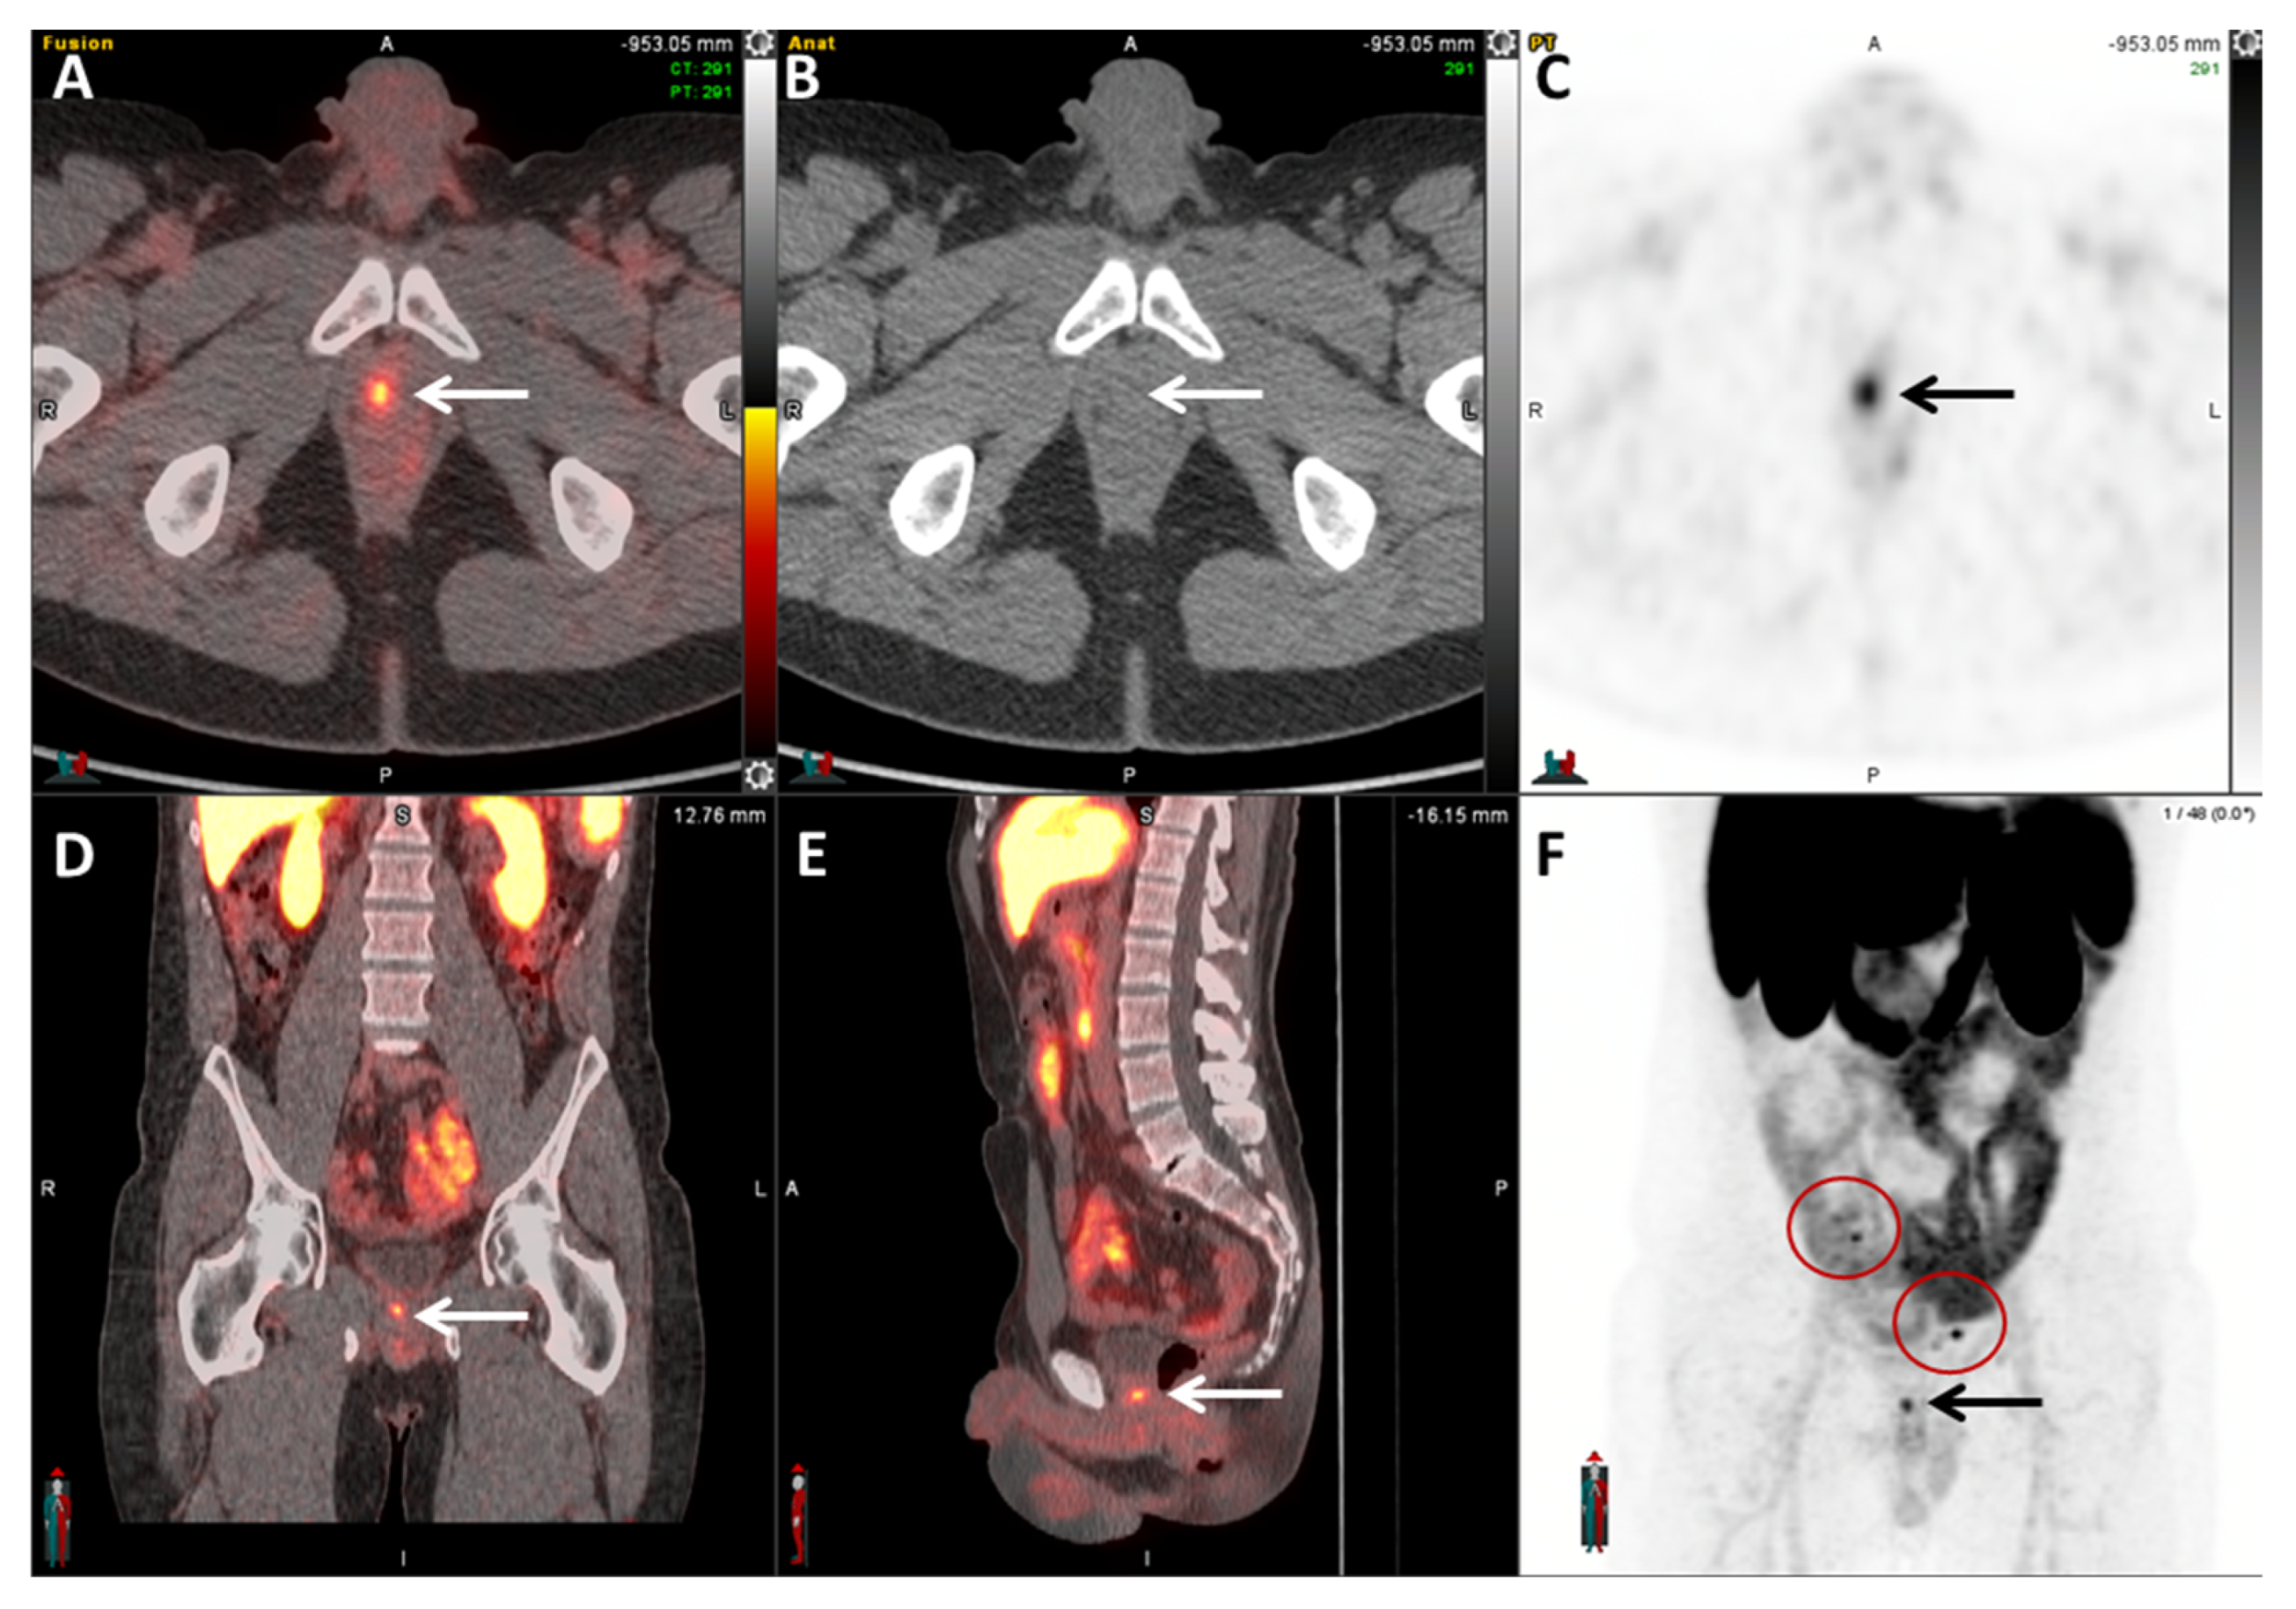

2.5.1. 68Ga-PSMA-11